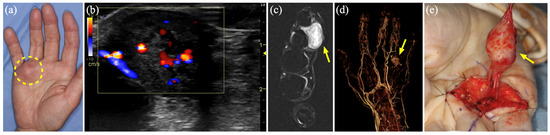

| 9 | 66 | M | Rt hand | AVM | US, MR, 3D-CTA | None | Angiomyoma | 19 |